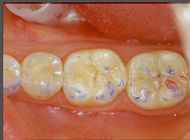

For Neuro Gnatologic Functional detail, rehabilitation model called 'NGF Index' from which a whole scientific process will be initiated which will lead to a diagnostic paradigmatic model called 'NGF Index' in the 'Extraordinary Science' section, means an occlusal adjustment normalized to trigeminal neuromotor symmetry . To achieve this goal, gnathological replicates (articulated) and above all the ability to read the evoked and reflex responses of the tCNS in different occlusal situations are fundamental. For this reason, only the active centrics of the Empress crowns were stratified on the four lower molars. (figure 7)

In figure 7a, b and c only the active centrics of the molars have been stratified because although the Centric Neuro Evocate Functional registration is of absolute precision, the mechanical transfer from the mouth to the laboratory (articulator) could incorporate minimal spatial variations. For this reason it was decided to stop the neuro-evoked closure of the slightly raised jaw in order to have the availability of the ceramic material to be remodeled following the trigeminal electrophysiological responses. In essence, the cusps were abraded sectorally and individually to then compare with the trigeminal electrophysiological responses up to the perfect symmetry and synchronicity of the tCNS. Once the result of symmetry and synchronism has been achieved, the position reached will become the incisal rod at zero to conclude the stratification.